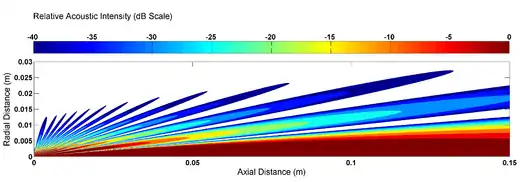

To illustrate the phenomena of side lobes in ultrasound beams, the resulting directivity function and acoustic intensity is calculated for a 1 MHz beam transmitted into water using a 1 cm radius transducer. Figure 2 plots the Directivity function, while Figure 3 plots the acoustic intensity relative to the intensity at the transducer surface.

For the purposes of diagnostic and therapeutic ultrasound the presence of side lobes is an undesirable effect. In diagnostic imaging wave reflection originating from the side lobes can be misinterpreted as reflections from the main beam, and act to reduce the resulting image quality. In therapeutic applications, side lobes represent energy dissipation on regions not intended to be effected. To reduce the effects of side lobes, ultrasound devices use transducer designs based on beamforming theory, making the analysis substantially more complicated than the simple cylindrical transducer discussed. One technique to reduce side lobes is the use of a phased array to focus the main at a particular depth, thus reducing the relative magnitude of side lobes. Another technique known as acoustic shadowing reduces side lobes by emitting lower amplitude waves near the edge of the transducer. As will be discussed in a proceeding section, an emerging technique to enhance focusing and reduce side lobes is the purposeful consideration of nonlinear acoustic effects in ultrasound beams.[1][11]